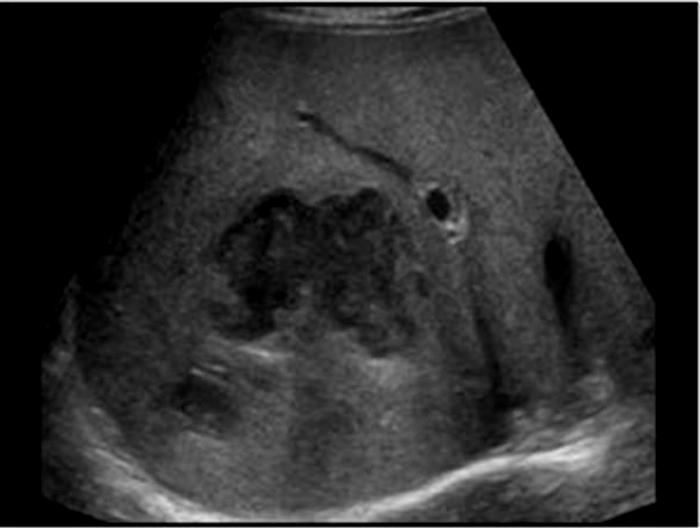

Caroli's Disease

congenital cystic dilatation of the intrahepatic biliary tree